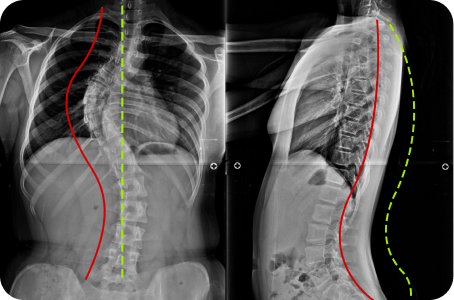

척추 엑스레이 검사

목 커브와 휘어짐 측정

좌우 어깨 높이와 틀어짐 측정

좌우 골반 수평 및 비틀림 측정

흉추,요추 만곡/ 척추 휘어짐 측정